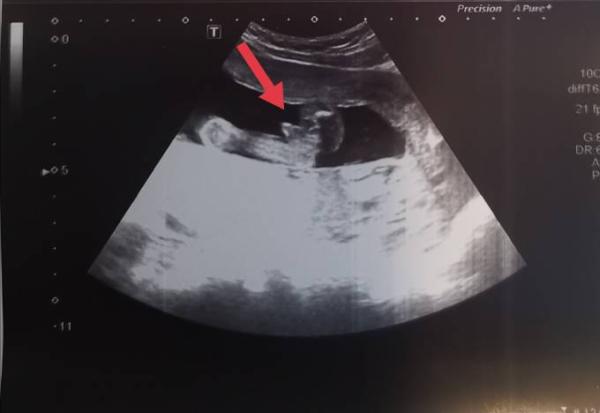

Ihr Lieben, was könnt ihr hier erkennen? Lt Arzt wird es eher ein Mädchen, schätzt ihr das auch so ein? DANKE!

Bild zu Junge oder Mädchen - SSW 22 - Forum für Juni - Mamis